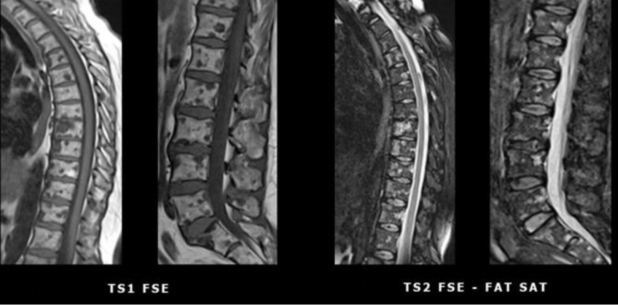

Tomografia computadorizada de tórax (fig. 2) e ressonância magnética (fig. 3), evidenciaram múltiplas formações nodulares ósseas aleatoriamente distribuídas em arcos costais e corpos vertebrais torácicos e lombares, sem sinais de fraturas patológicas. Biópsia (fig. 4) e estudo imunohistoquimico (fig. 5) foram realizados; a análise histológica revelou medula óssea com celularidade preservada e sem evidência de malignidade. A imunohistoquímica (IHQ) demonstrou expressão para CD3 e CD20 sem expressão de citoqueratina, sugerindo tecido hematopoiético reacional e excluindo neoplasia secundária.

Como geralmente é clinicamente assintomática, os achados indicativos de OPQ são tipicamente detectados incidentalmente em exames de imagem durante a investigação de outra condição concomitante(1-3). Caracteristicamente, essas lesões são numerosas, pequenas (1-10 mm), homogêneas, escleróticas, circulares ou ovaladas, bem delimitadas, com ausência de destruição óssea(1,4,5,10). Apresentam-se como ilhas ósseas difusas e simétricas, cujos locais mais comuns são as falanges da mão, seguidas por ossos do carpo, metacarpos, falanges dos pés, metatarsos, ossos do tarso, pelve e epífises e metáfises de ossos longos(2,3,8).

O principal diagnóstico diferencial são metástases osteoblásticas. Neste caso, posto que a paciente era portadora de carcinoma invasivo de mama, essa foi a primeira hipótese aventada. Porém, análises posteriores fortaleceram a possibilidade de uma condição benigna em detrimento a metástases neoplásicas. Em relação ao câncer de mama, até 70% das metástases são esqueléticas, podendo apresentar aspecto radiológico lítico, blástico ou misto(7). Em contraste à OPQ, as lesões metastáticas osteoblásticas tendem a ser assimétricas de tamanhos variados e a apresentar destruição óssea e reação periosteal(3,4,7). São vistas com maior frequência em costelas, corpos vertebrais e diáfises de ossos longos(1-3). Outros diagnósticos diferenciais da OPQ incluem mastocitose e esclerose tuberosa. Em ambas estas condições, as lesões tendem a apresentar menor preferência metafisária e epifisária e a ser mais assimétricas e mal definidas(3,6).